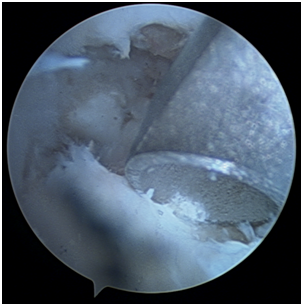

The arthroscopic procedure started with the realization of standard radio-carpic initial portals; medium-carpal portals helped with the identification of the pseudarthrosis focus (Figure 4). The pseudarthrosis focus was blown out (Figures 5 & 6). The spongious graft of the contralateral iliac crest was harvested. Placement of the graft through the midcarpal portal of visualization by adapting the arthroscopy trocar (Figures 7-9). The traction was withdrawn. The graft was fixated with a percutaneous anterior approach and arthroscopic support and placement of the double compression screw with radiographic support (Figure 10).

Figure 4 Arthroscopic view of pseudarthrosis.